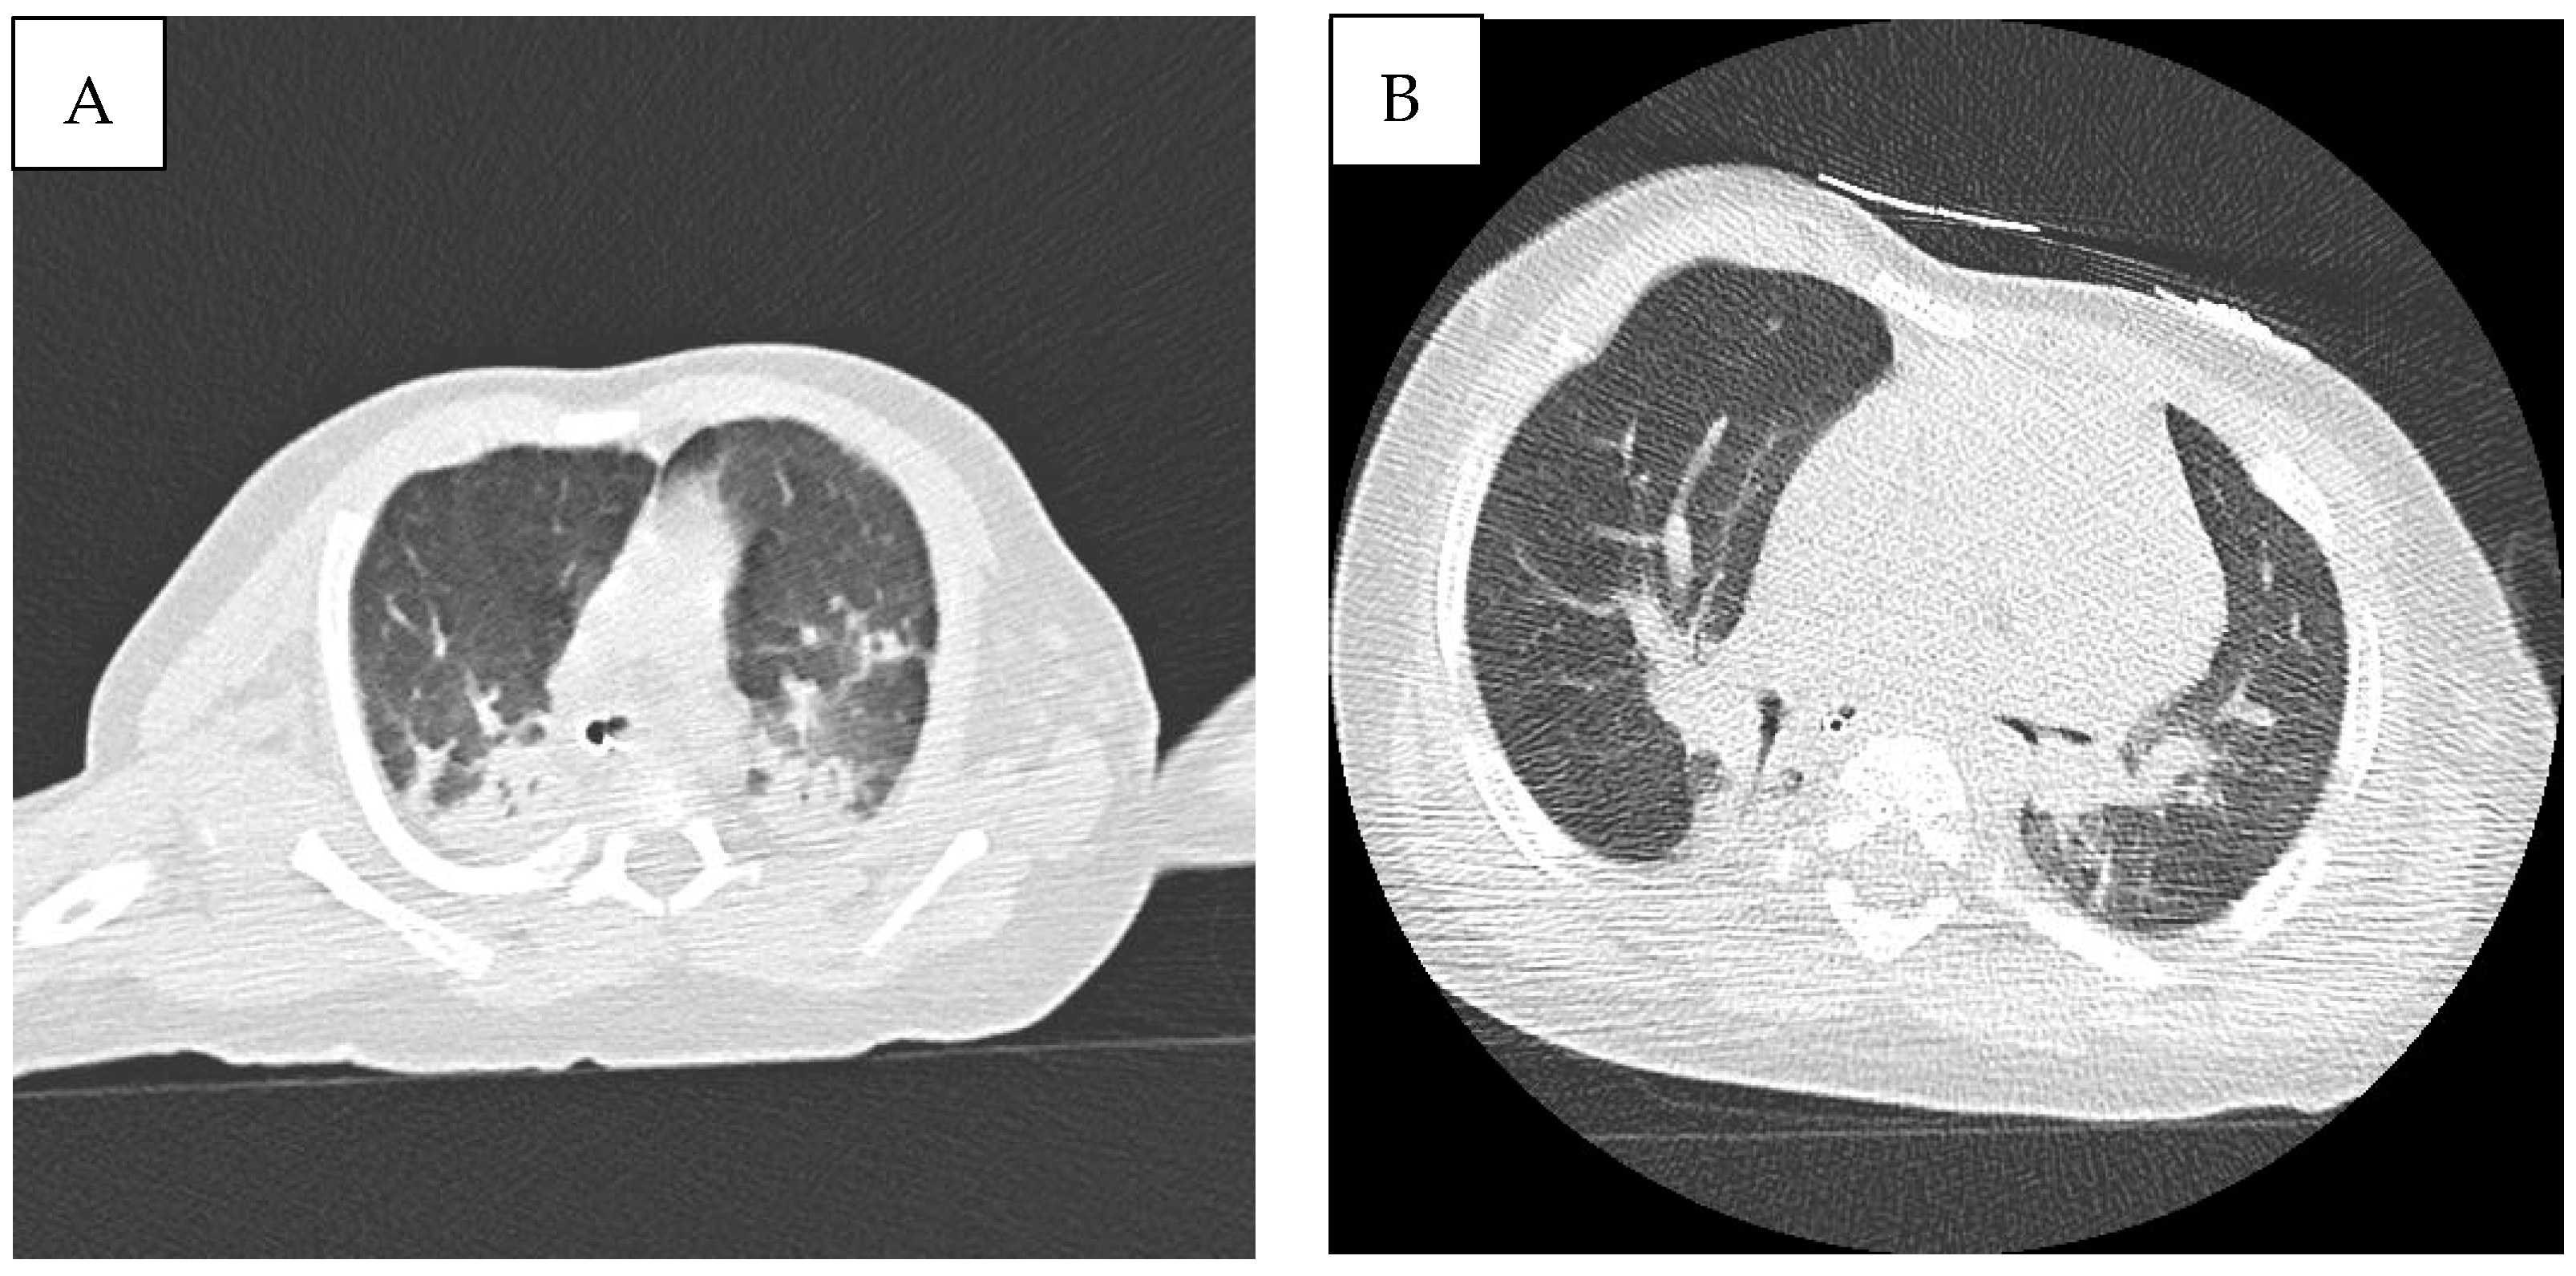

2. Case Description